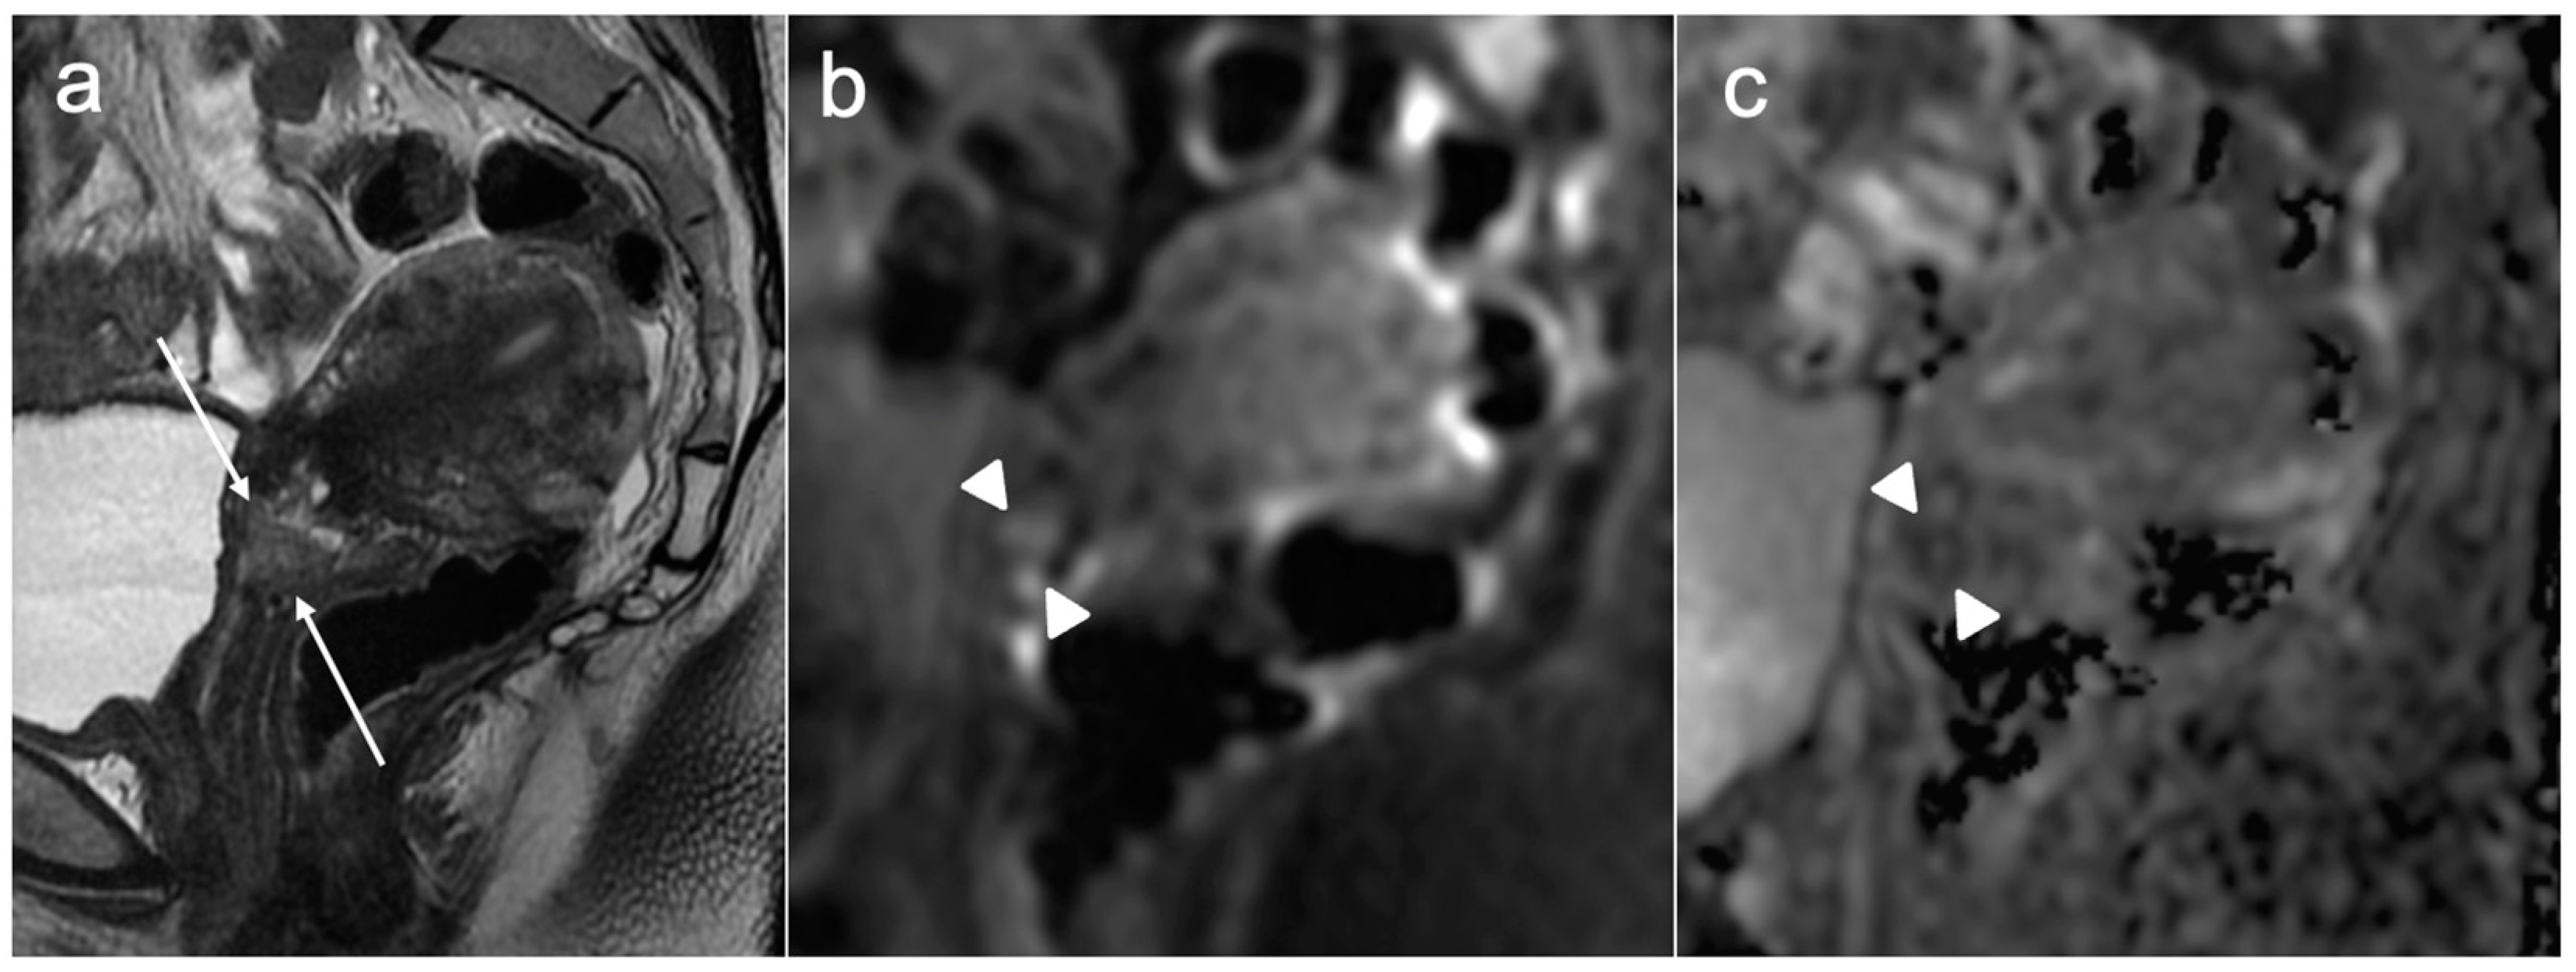

| IIB | With parametrial invasion but not up to the pelvic wall |

| Stage III | Involves the lower third of the vagina and/or extends to the pelvic wall and/or causes hydronephrosis or non-functioning kidney and/or involves pelvic and/or paraaortic lymph nodes |

| IIIA | Involves lower third of the vagina, with no extension to the pelvic wall |

| IIIB | Extension to the pelvic wall and/or hydronephrosis or non-functioning kidney (unless known to be due to another cause) |